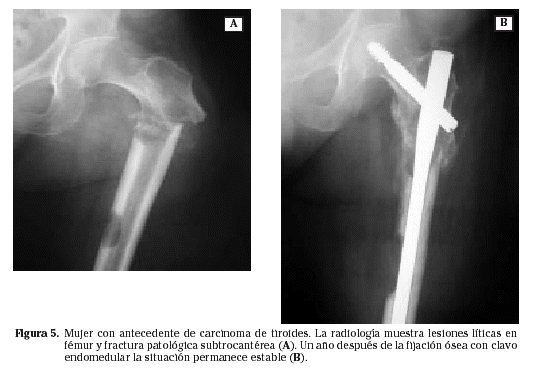

En las metástasis óseas diafisarias el tratamiento consiste en una ostesíntesis lo más amplia y estable posible del hueso, que cubra todas las áreas de debilidad, anticipándose incluso a la progresión previsible de la enfermedad (Figs. 5 y 6).